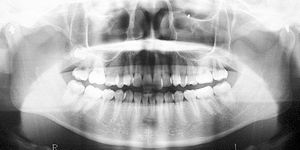

健康な小臼歯を抜いていません

矯正前                 矯正後

治療前 の レントゲン です 動く矢印治療後 の 歯列レントゲン です